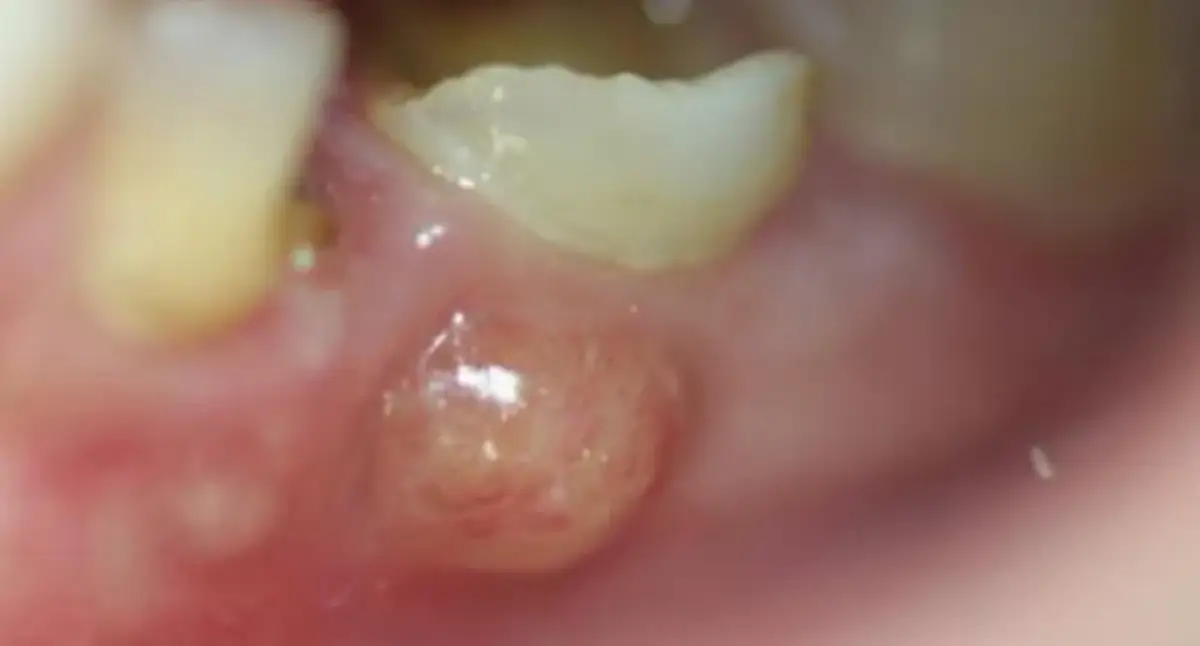

- Ropa na dziąśle objawia się jako biały lub żółtawy pęcherzyk, guzek, zaczerwienienie i obrzęk, często z pulsującym bólem.

Ropa na dziąśle to zazwyczaj objaw obecności ropnia, czyli ograniczonego zbiornika treści ropnej powstałego w wyniku infekcji bakteryjnej. Wizualnie może przybierać różne formy od małego, białego lub żółtawego pęcherzyka, przez niewielką krostę, aż po wyraźne zgrubienie czy guzek na tkance dziąsła. Miejsce to jest często zaczerwienione i obrzęknięte, co świadczy o toczącym się stanie zapalnym. Konsystencja treści ropnej jest zazwyczaj gęsta. Ważne jest, aby odróżnić ropień od innych zmian w jamie ustnej, takich jak na przykład afty, które są zazwyczaj bardziej płaskie, owalne i mają białawy środek otoczony czerwoną obwódką, a ich przyczyną nie jest infekcja bakteryjna w takim stopniu jak w przypadku ropnia.